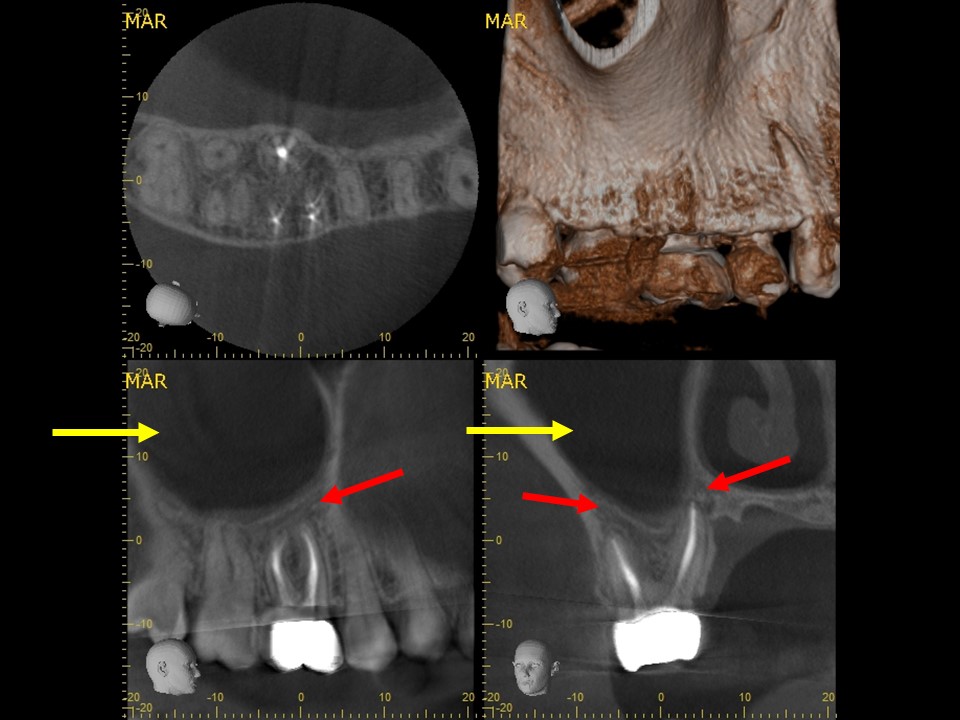

| 治療前レントゲン | 治療前CT |

![]() |

術前のレントゲンおよびCT画像です。根尖部に根尖病変と思われるX線透過像を認めます(黄矢印)。歯根の側方には、方向を間違えて削ったと思われる跡が見られます。